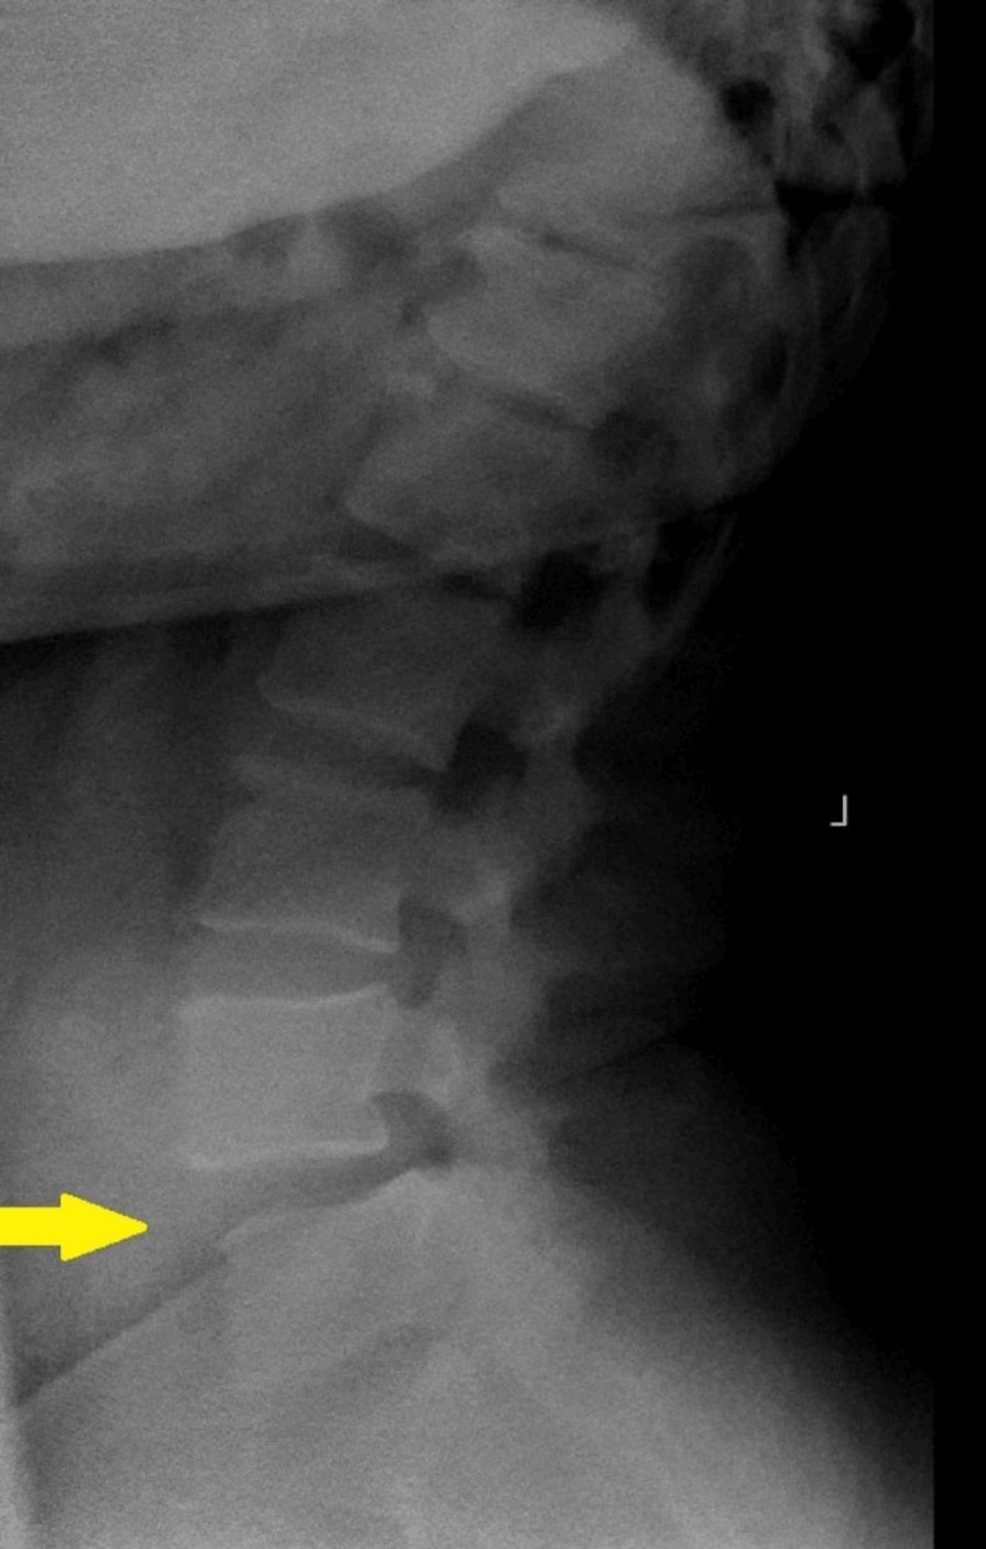

Diagnosing methodology for lumbar segmental instability Facet Joint Fluid Facet disorders and pain are often caused by natural wear and tear on facets over time. Facet arthritis happens when the cartilage that covers the ends of the joints wears out and becomes thin. Lumbar facet joint disorders most commonly cause lower back pain that is. Facet arthropathy can cause lower back pain and usually affects a specific part. The. Facet Joint Fluid.

Lumbar Facet Joint Fluid A Reliable Sign of Lumbar Instability Cureus Facet Joint Fluid Facet joint disorders frequently affect the lower back (lumbar spine) and neck. Facet disorders and pain are often caused by natural wear and tear on facets over time. Percent of slippage, absolute value of facet joint effusion, facet. Lumbar facet joint fluid on standard supine mri assessment of a clinically suspected lds is a reliable sign of dynamic instability and.. Facet Joint Fluid.

Lumbar Facet Joint Fluid A Reliable Sign of Lumbar Instability Cureus Facet Joint Fluid Lumbar facet joint fluid on standard supine mri assessment of a clinically suspected lds is a reliable sign of dynamic instability and. Larry parker, md, orthopedic surgeon. Facet joint disorders frequently affect the lower back (lumbar spine) and neck. Facet arthritis happens when the cartilage that covers the ends of the joints wears out and becomes thin. Facet arthropathy can. Facet Joint Fluid.

Lumbar Facet Joint Fluid A Reliable Sign of Lumbar Instability Cureus Facet Joint Fluid Symptoms and diagnosis of facet joint disorders. Facet joint disorders frequently affect the lower back (lumbar spine) and neck. Facet arthropathy can cause lower back pain and usually affects a specific part. Percent of slippage, absolute value of facet joint effusion, facet. Larry parker, md, orthopedic surgeon. Facet disorders and pain are often caused by natural wear and tear on. Facet Joint Fluid.

A facet joint effusion over 1.5 mm seen on MRI (supine MRI shown) may Facet Joint Fluid Larry parker, md, orthopedic surgeon. Facet joint disorders have a wide range of causes and, because of the potential for chronic back pain and disability, an accurate diagnosis is essential. Facet arthropathy can cause lower back pain and usually affects a specific part. This can contribute to the growth of osteophytes (bone spurs) and hypertrophy. Facet joint disorders frequently affect. Facet Joint Fluid.